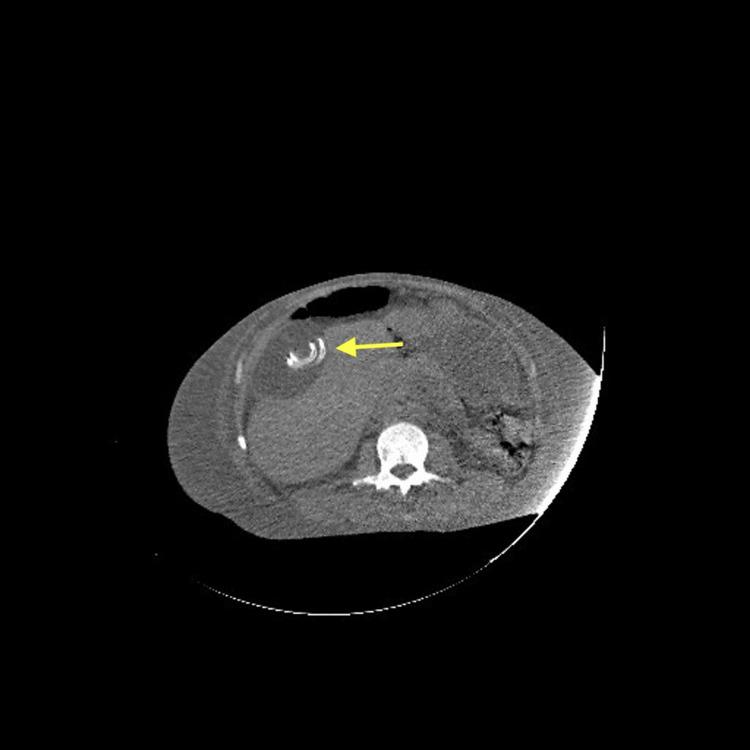

We report an intriguing case of an incidental abdominal pseudocyst in a patient undergoing long-term peritoneal dialysis. Although pseudocysts are rare, they represent a significant complication in peritoneal dialysis patients, often arising secondary to chronic peritoneal inflammation, peritonitis episodes, or catheter-related factors. In this case, the pseudocyst was an incidental finding on imaging, with no immediate symptoms but potential implications for dialysis efficacy and future intra-abdominal complications. The case underscores the importance of vigilant imaging assessment and multidisciplinary management to monitor such lesions and prevent progression to more serious issues, including infection or loss of dialysis access. Recognizing these pseudocysts is critical for optimizing ongoing management and preserving peritoneal dialysis as a feasible treatment modality.

https://cdn.ncbi.nlm.nih.gov/pmc/blobs/a42c/12278785/cd5e0449770f/cureus-0017-00000088008-i01.jpg